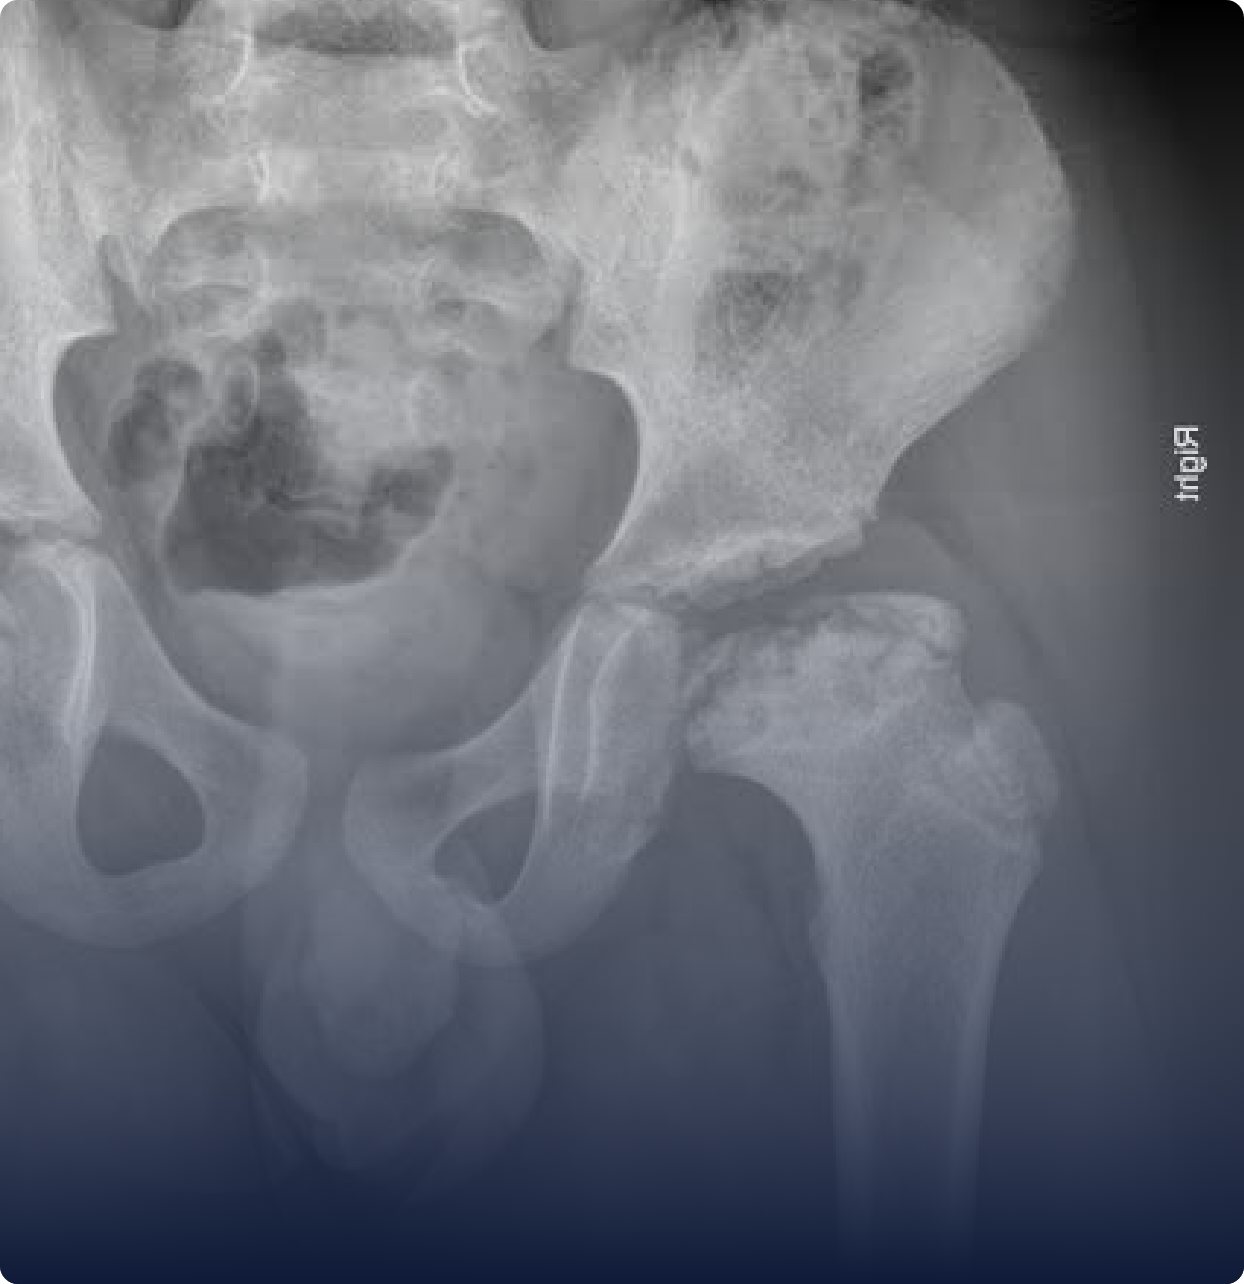

Doença de Perthes

É uma condição em que há interrupção temporária da circulação sanguínea na cabeça do fêmur, o que leva à necrose óssea. Isso pode causar dor, mancar e limitar os movimentos do quadril da criança.